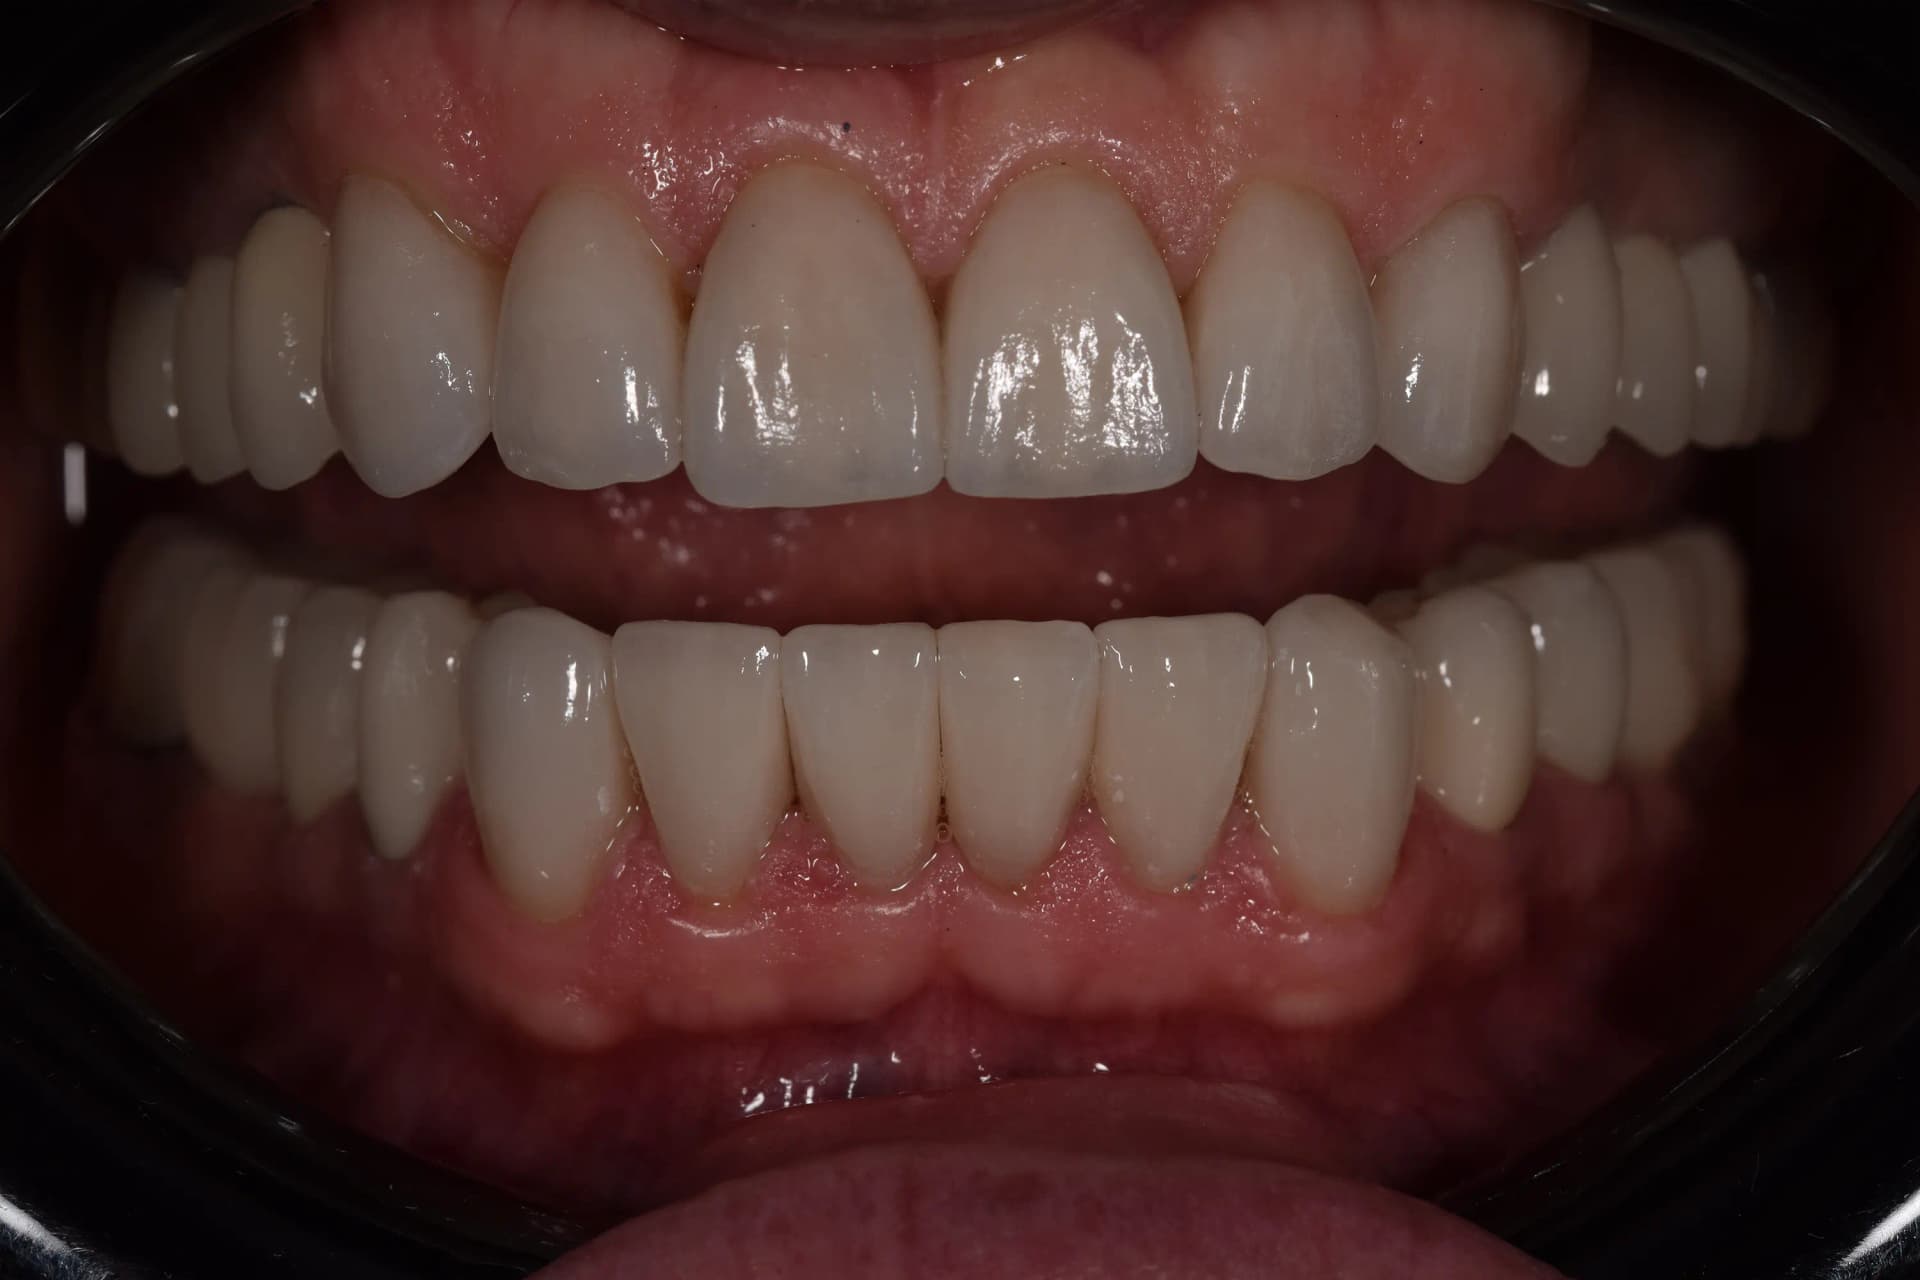

Rezultat

Finalul tratamentului a adus o transformare spectaculoasă. Pacientul se bucură acum de un zâmbet luminos, cu dinți aliniați armonios și cu o formă naturală refăcută. Am reușit să „ștergem” ani buni de pe chipul pacientului prin corectarea liniei zâmbetului și eliminarea aspectului de dinți tociți, oferindu-i un aspect întinerit și o funcționalitate impecabilă a mușcăturii.